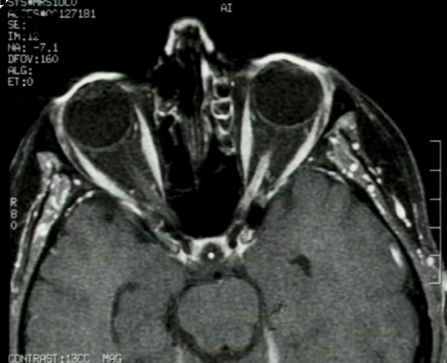

What is your diagnosis?

Note that the patient’s left optic nerve is brighter (enhanced by gadolinium), which is abnormal because it does not have a BBB. The size of CN II is normal so the patient has optic neuritis.